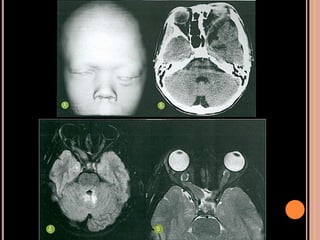

SÍNDROME PHACE

 Posterior fossa malformations

 Hemangiomas

 Arterial anomalies

 Coarctation of the aorta

 Eye anomalities

 S (sternum, supraumbilical raphe)

Pode coexistir defeitos no desenvolvimento ventral

(fendas no esterno e da rafe supraumbilical;

SÍNDROME DE PHACE

Achados clínicos

Hemangioma facial grande, em placa, por vezes

ulcerado; principalmente V1 do trigêmio; ao

nascimento

Cefaleia, crises epilépticas, alteração no

desenvolvimento, hemiparesia;

Coarctação de aorta;

Recomendações

 Todos os pacientes com hemangioma facial devem

ser submetidos ao estudo com RM;

 Casos menos graves provavelmente são muito

mais comuns do que se pensa;

 Suspeita de PHACE  fossa posterior, angio TC,

angio RM do arco aórtico, cervicais, intracranianas;